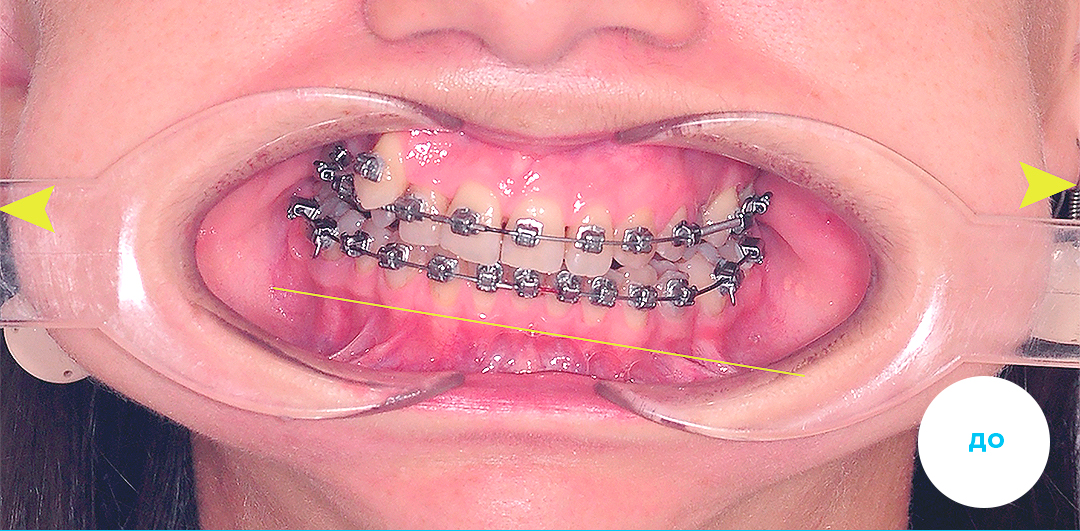

Работы специалиста